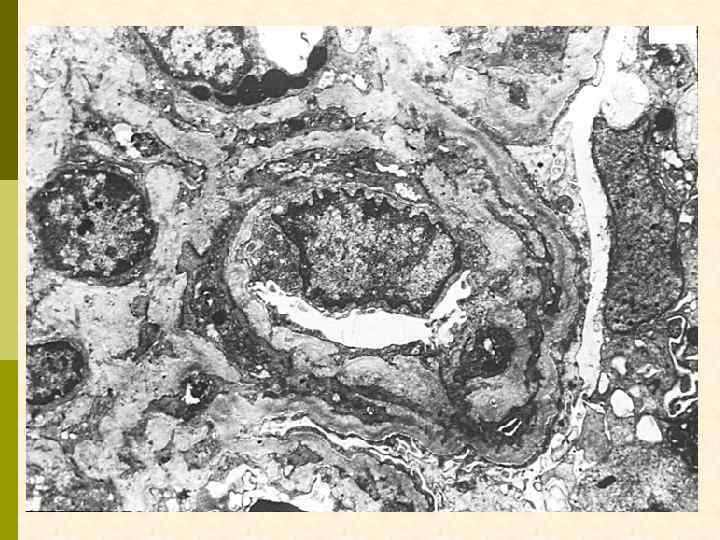

МПГН-III (вариант Strife and Anders).

Гистологические варианты МПГН q Тип I – хроническая иммунокомплексная болезнь q иммунные депозиты в мезангии и субэндотелии q ассоциируется с гепатитом С, смешанной криоглобулинемией, гепатитом В, бактериальным эндокардитом q Тип II – болезнь плотных депозитов q С 3 при иммунофлуоресценции, но без иммуноглобулинов q аутоантитела к С 3 конвертирующему ферменту (C 3 Nef) q в 90% случаев рецидивирует в трансплантате q Тип III – хроническая иммунокомплексная болезнь q в отличие от I типа имеются субэпителиальные депозиты и разрушение базальной мембраны с прозрачными лакунами